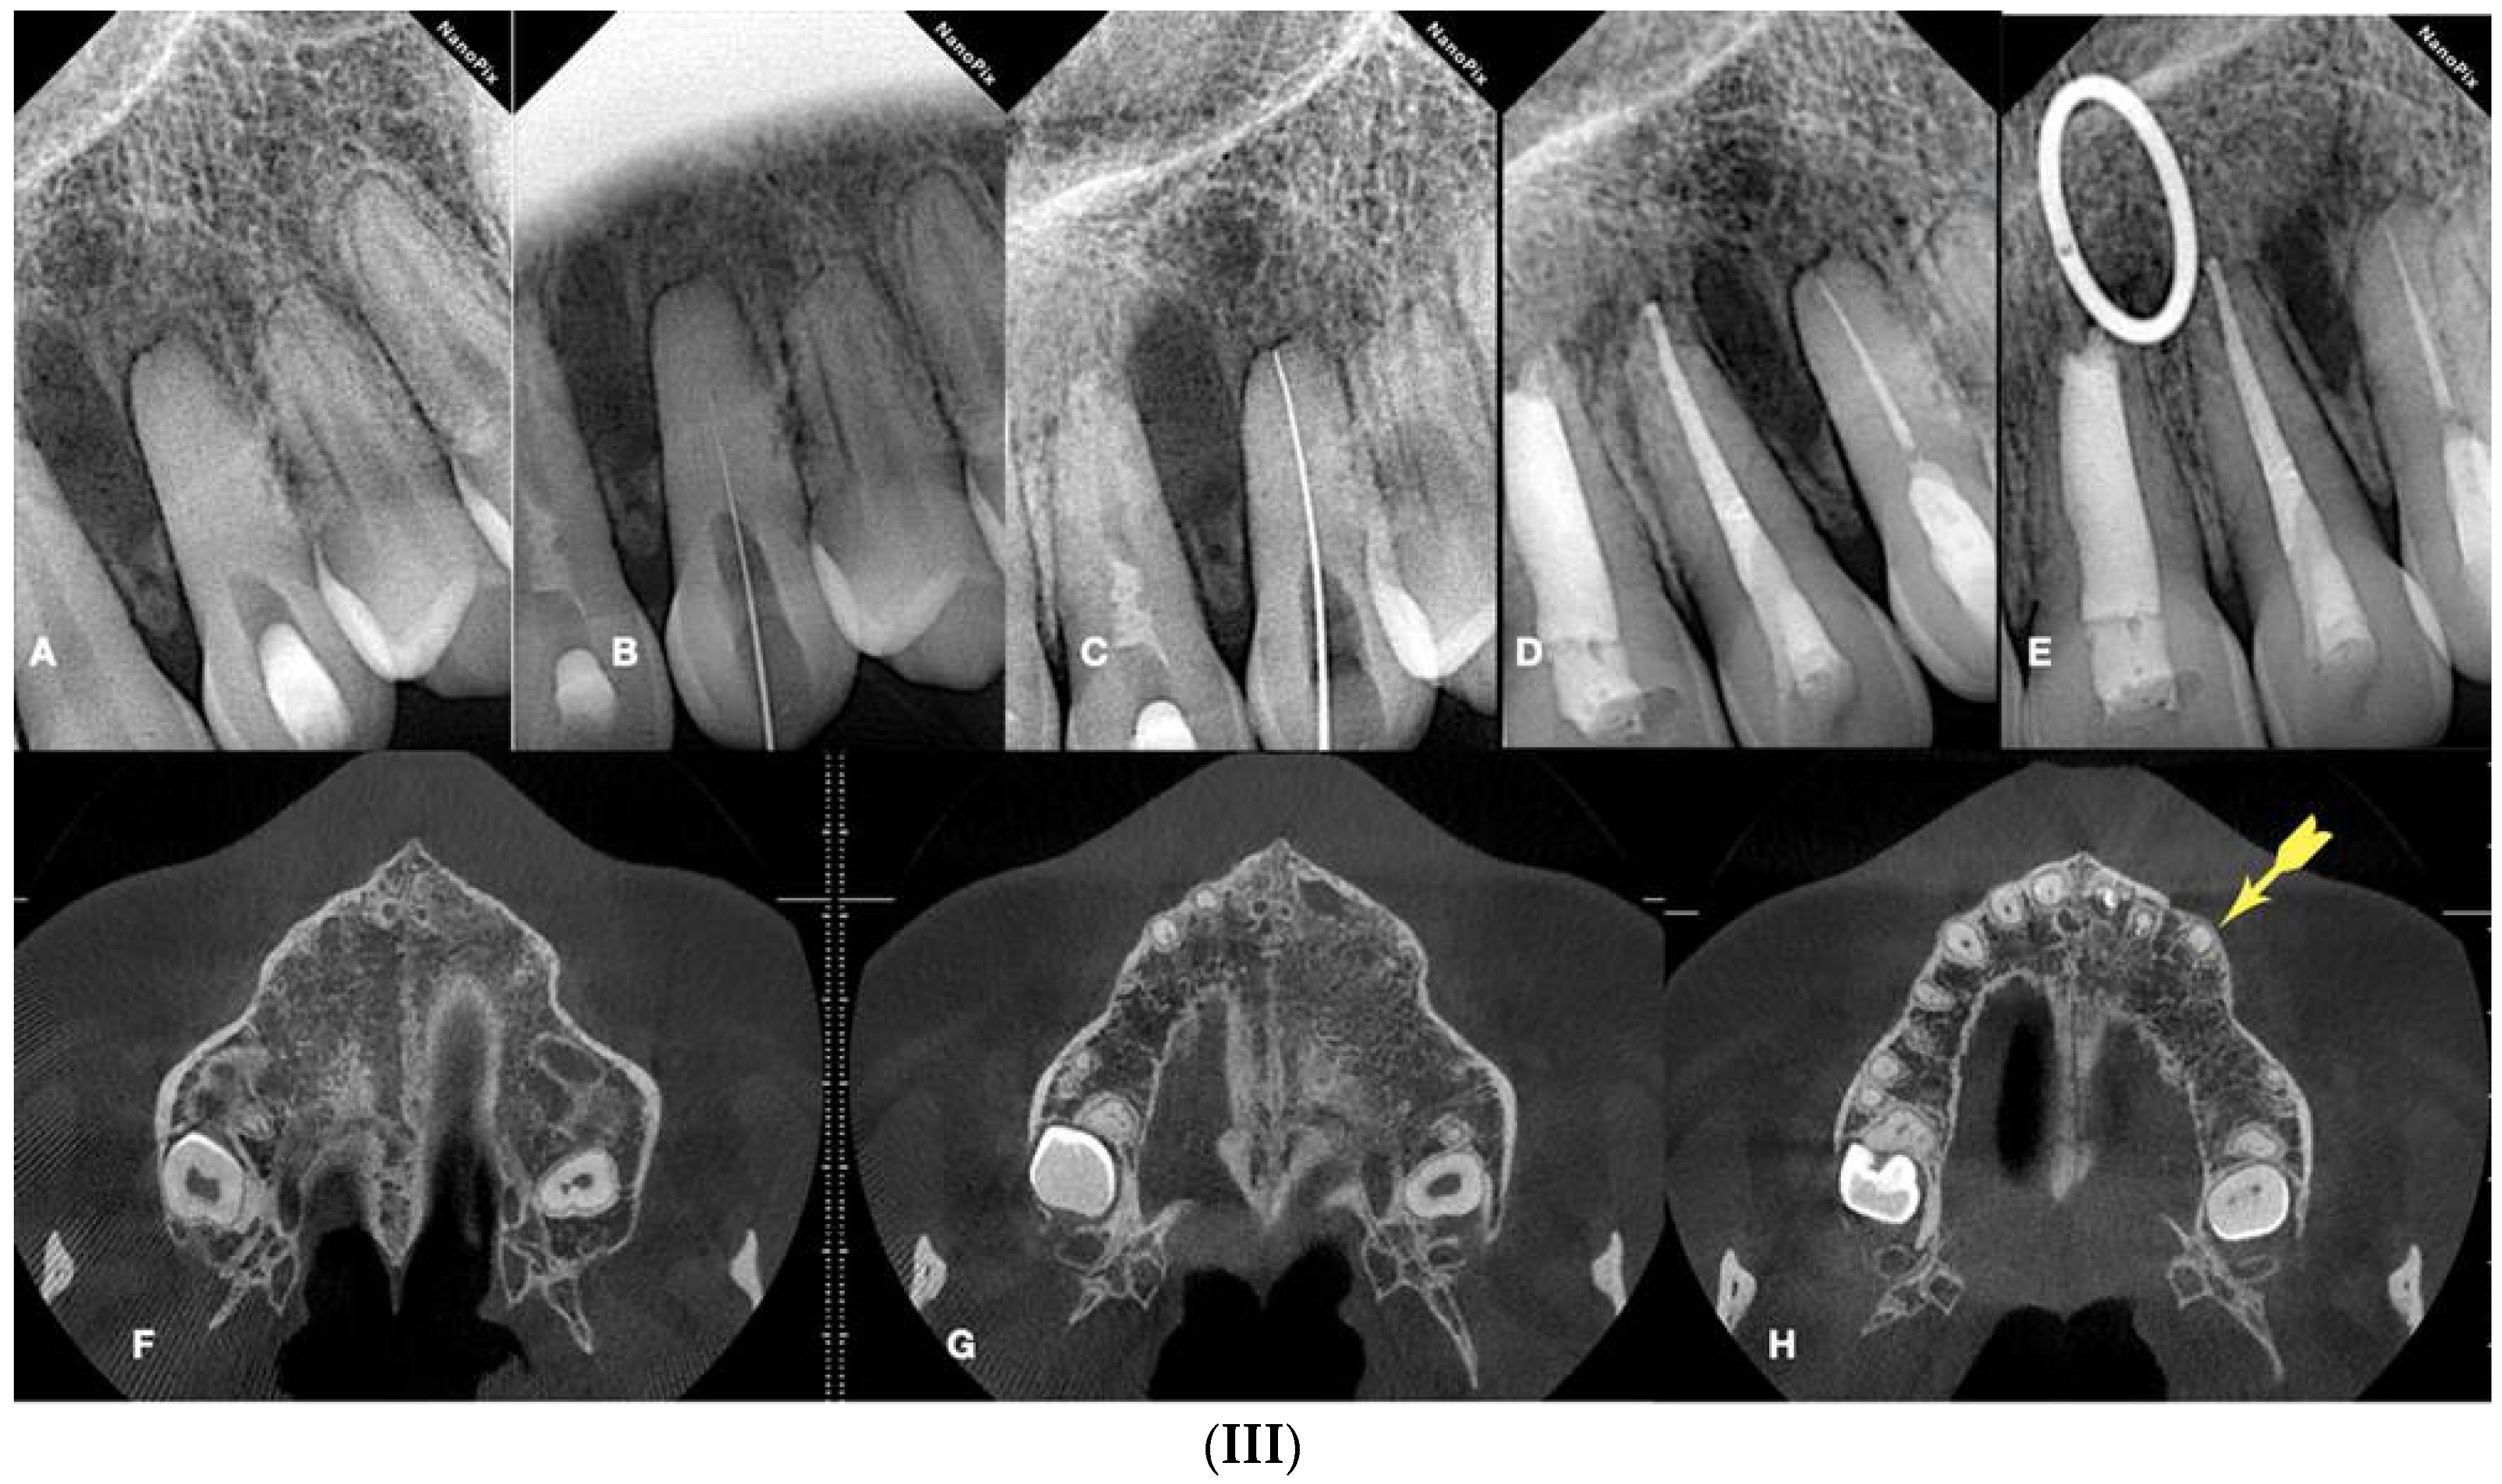

Radiographically, CM is categorized into partial calcification, where the pulp chamber is occluded, and the canal is constricted but detectable, and complete calcification, where both the pulp chamber and canal are hardly or not detectable. Despite the radiographic appearance, histological and micro-ct studies suggest the presence of a narrow canal, regardless of its visibility on radiographs (Figure 1 and Figure 2).

(A) Periapical radiograph of an abraded calcified mandibular incisor with no visible canal lumen. (B) Three-dimensional micro-ct reconstruction of the same calcified mandibular incisor that was extracted for prosthetic reasons. The micro-ct reveals a patent canal. (C) Apical root canal anatomy of the calcified canal lumen sectioned, revealing canal bifurcation and apical anastomosis (Skyscan 1172 micro-CT scanning device, Bruker MicroCT, Belgium) (images courtesy of Dr. Alexey Volokitin, city of Dnepr, Ukraine).

Figure 2.

Axial micro-ct slices of the calcified mandibular incisor of Figure 1 reveal the cross-sectional root canal dimensions along the root. The crown of the tooth is completely blocked, and the canal is visible starting at the level of the CEJ. The root canal dimensions are constricted along the coronal part of the root, becoming wider in the middle, followed by an apical splitting into two canals. Calcified cases usually present an inverted taper (Skyscan 1172 micro-CT scanning device, Bruker MicroCT, Belgium) (images courtesy of Dr. Alexey Volokitin, city of Dnepr, Ukraine).